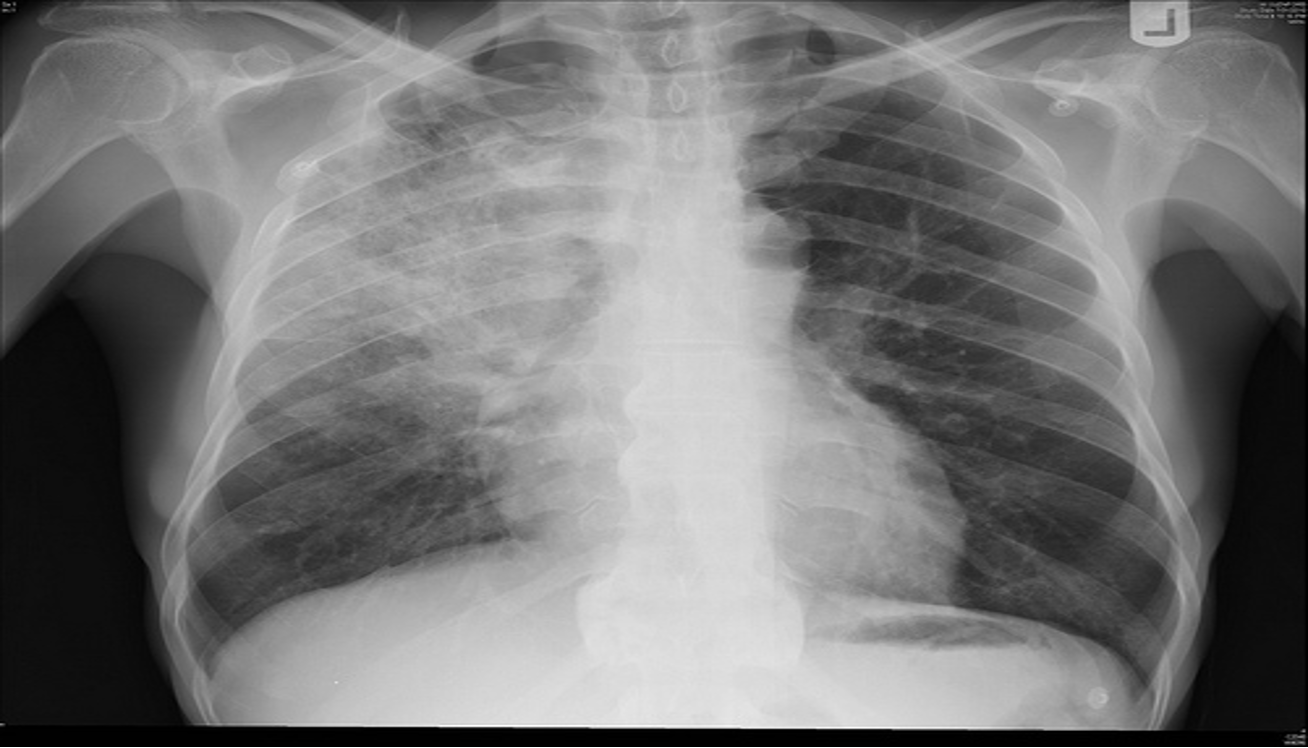

- CXR:

- The appearance of consolidation on CXR is reliable for the diagnosis of pneumonia, but CXR appearances are not reliable for distinguishing between viral and bacterial infection as there is considerable overlap.

- The CXR may appear normal early in the disease. However, as an approximate guide:

- Viral pneumonia:

- Patchy perihilar infiltration, hyperinflation, atelectasis

- Bacterial pneumonia:

- Lobar consolidation (air bronchogram) occasionally with parapneumonic effusion. Pneumatocoele and abscesses suggest staphylococcal pneumonia

Chest X-Ray showing patch of pneumonia

Image of chest x-ray displaying the interstitial pattern seen in viral pneumonia. The interstitial pattern shows fine lines radiating from the hila.

These chest X rays compare clear, healthy lungs with the cloudy, inflamed lung tissue of pneumonia.

Right lower lobe consolidation in a patient with bacterial pneumonia.